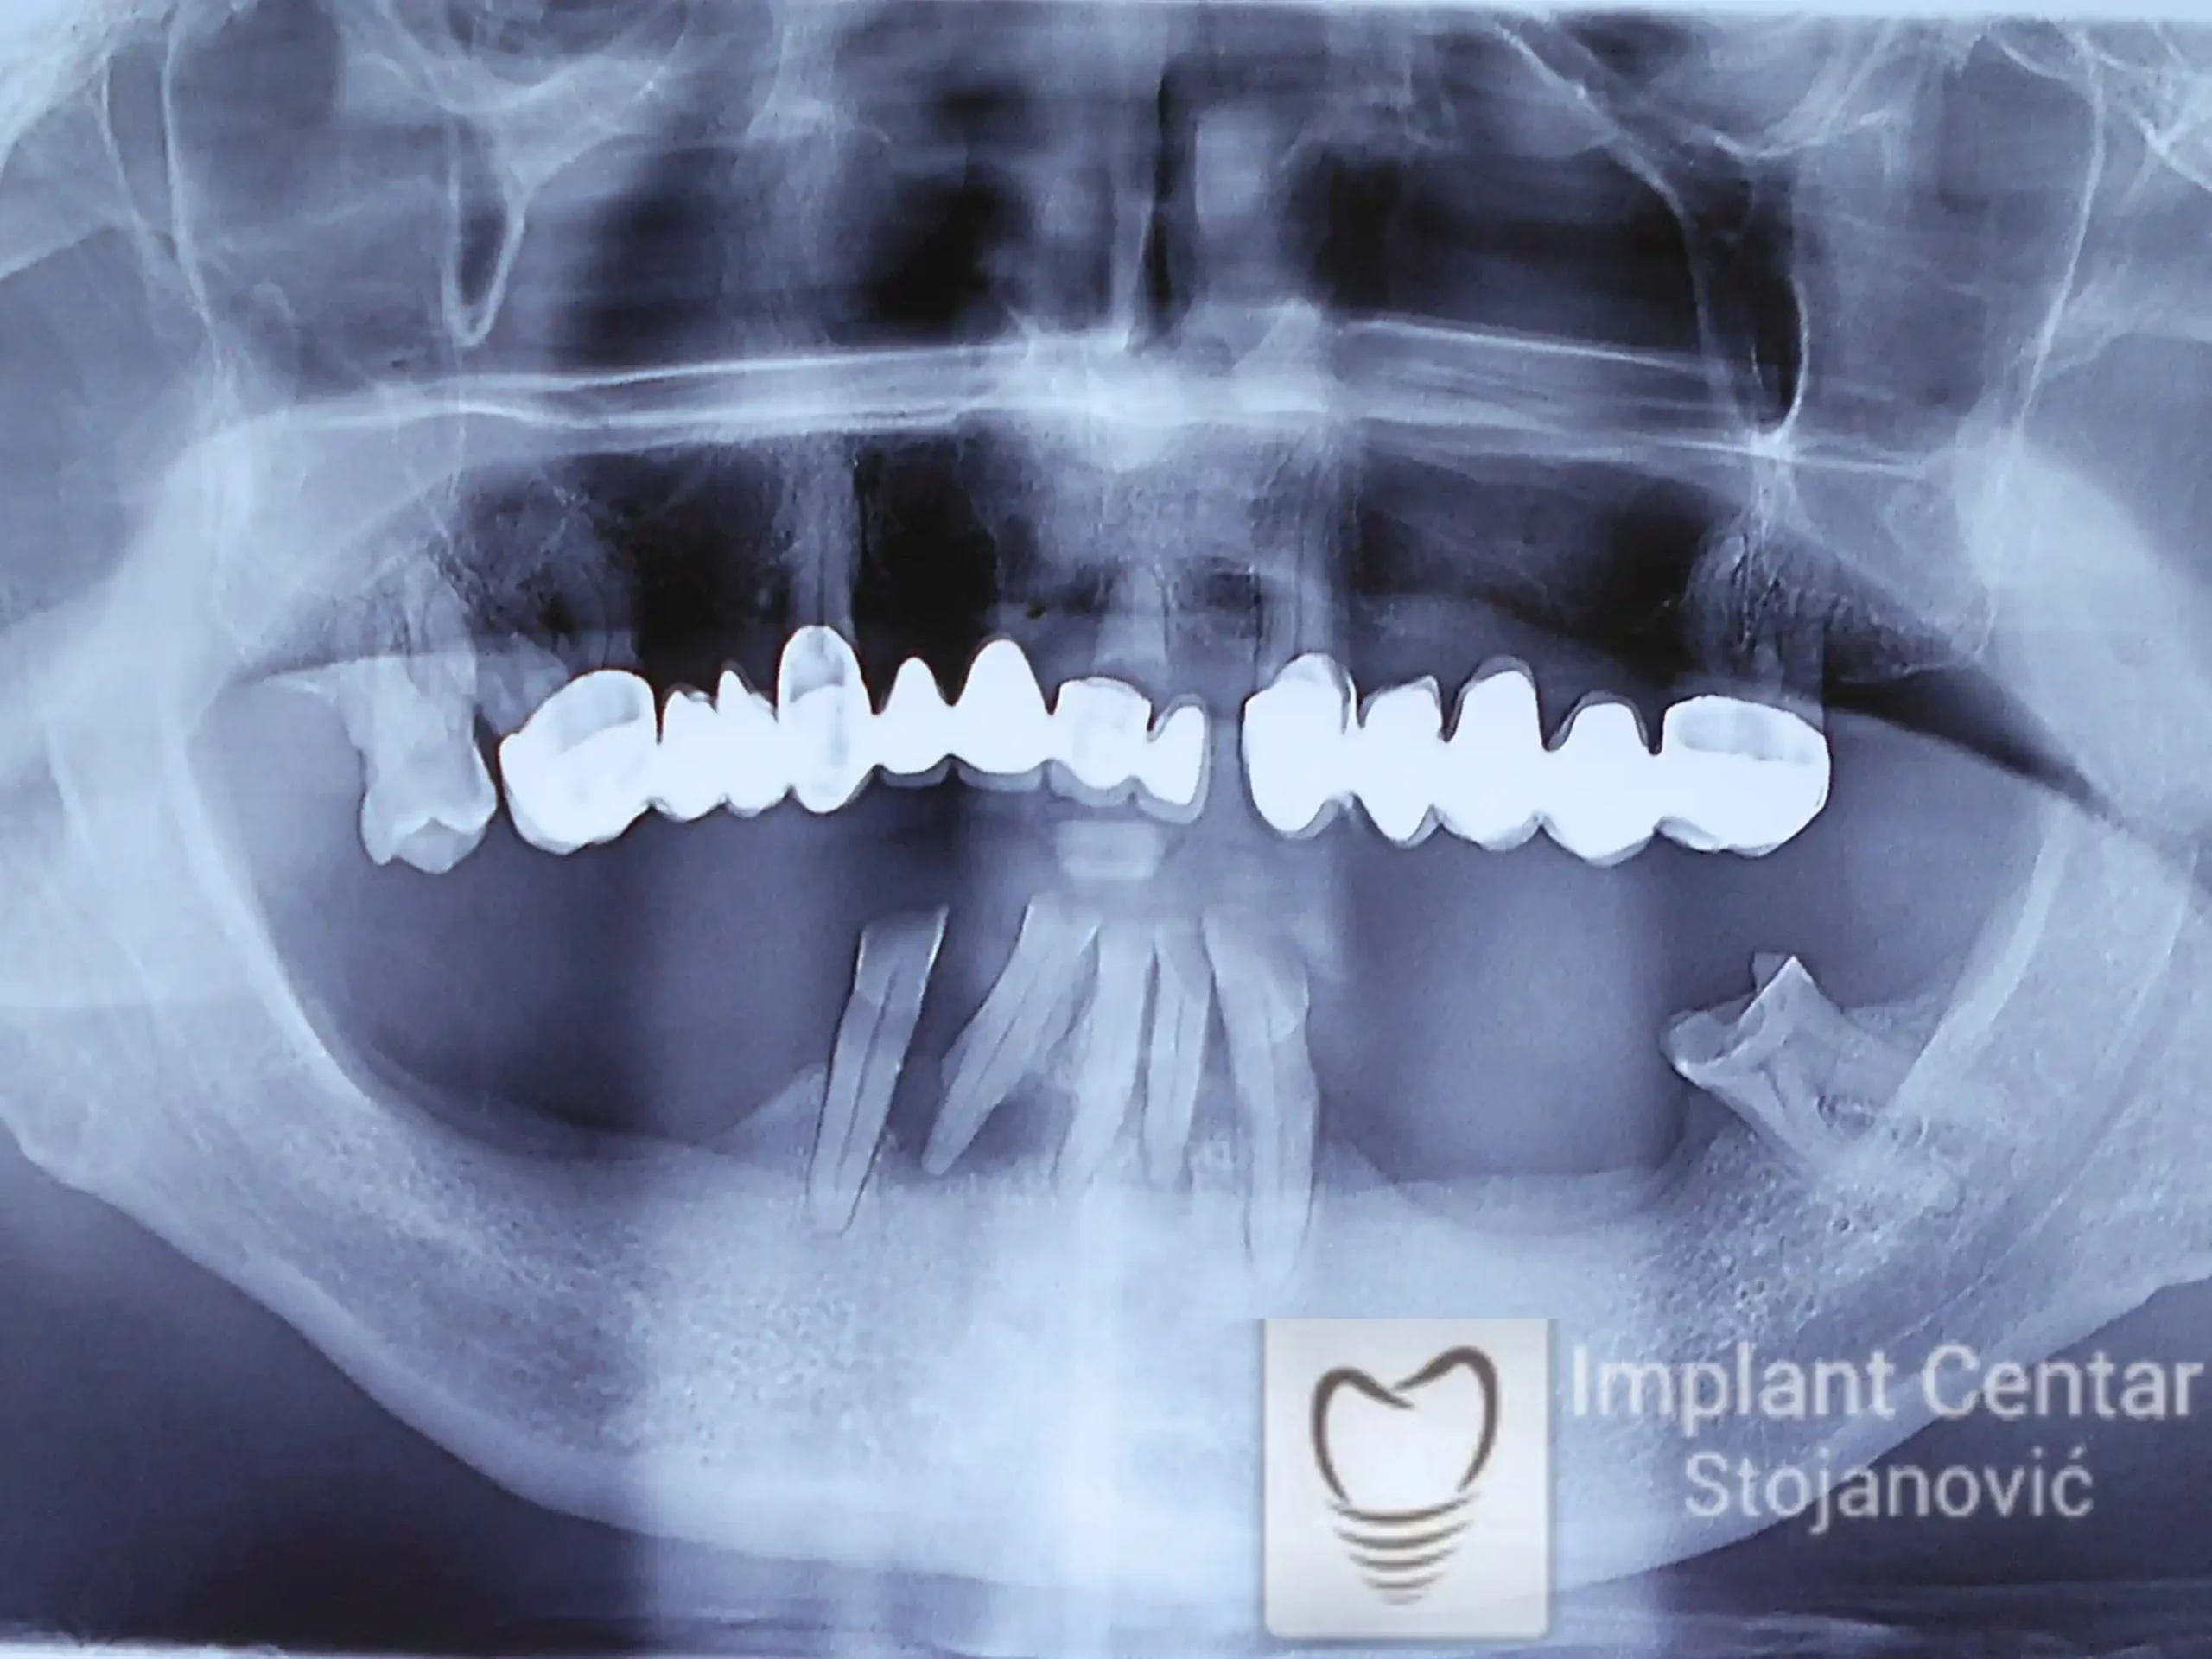

Na slici 1. slici 2. vidi se početno stanje — pacijent je imao prirodne zube, ali samo izradom novih mostova nije bilo moguće postići normalan odnos gornjih i donjih zuba (eugnatan zagrižaj).

Zbog toga je plan terapije uključivao vađenje svih preostalih zuba i ugradnju implantata u gornjoj i donjoj vilici. U gornjoj vilici postavljena su i dva tuberopterigoidna implantata, kao zamena za sinus lift proceduru, što se može videti na ortopan snimku nurađenom odmah nakon ugradnje (slika 3).

Na slici 1. i slici 2. prikazan je izgled pacijenta pre početka terapije – klinički i rendgenološki.

Nakon vađenja zuba, ugrađeni su implantati. Na slici 3 prikazan je ortopan snimak sa ugrđenim implantatima. Tokom perioda osteointegracije, pacijent je bio zbrinut fiksnim privremenim krunicama na implantatima, koje su izrađene samo dva dana nakon hirurške intervencije.